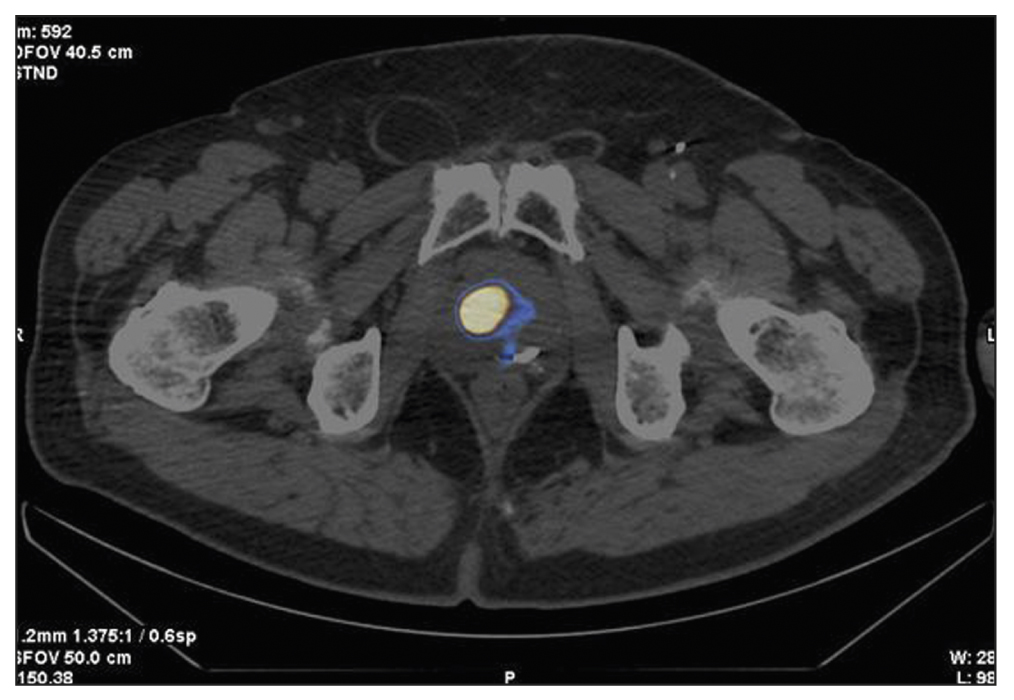

Case report 4

Patient F., 68 years old, was admitted with prostate cancer, T3a, which had spread to the prostate gland capsule. In 2013, 125I sources were implanted into the prostate tissue and the extracapsular area. PSA has increased since the end of 2020. SPECT/CT was performed using 99mTc-HYNIC-PSMA due to an increased PSA level of 0.95–2.8 ng/mL after the previous treatment (Figure 5). SPECT/CT revealed a 15-mm3 site of tumor tropic RP accumulation, which was biopsied under the CT guide. A histological diagnosis was prostate adenocarcinoma, Gleason 6 (3 + 3). Dosimetry planning for low-dose brachytherapy was performed using SPECT/CT. On November 03, 2021, 125I microsources were re-implanted according to topometric markings to implement the dosimetry plan. The PSA level was 0.05 ng/mL during the follow-up examination (January 23, 2023).

Fig. 5. Patient F., 68 years old, SPECT/CT with 99mTc-HYNIC-PSMA: Sites of radiopharmaceutical accumulation at the border of the central zone and the posterolateral part of the peripheral zone on the right side at the level of the base of the right prostate lobe. The scan visualizes multiple rods in the prostate gland, implanted during previous brachytherapy.

In this case, SPECT/CT with 99mTc-HYNIC-PSMA allowed for a precision biopsy, which confirmed the local recurrence of prostate cancer and subsequently enabled brachytherapy to be repeated (salvage) under the CT guide.